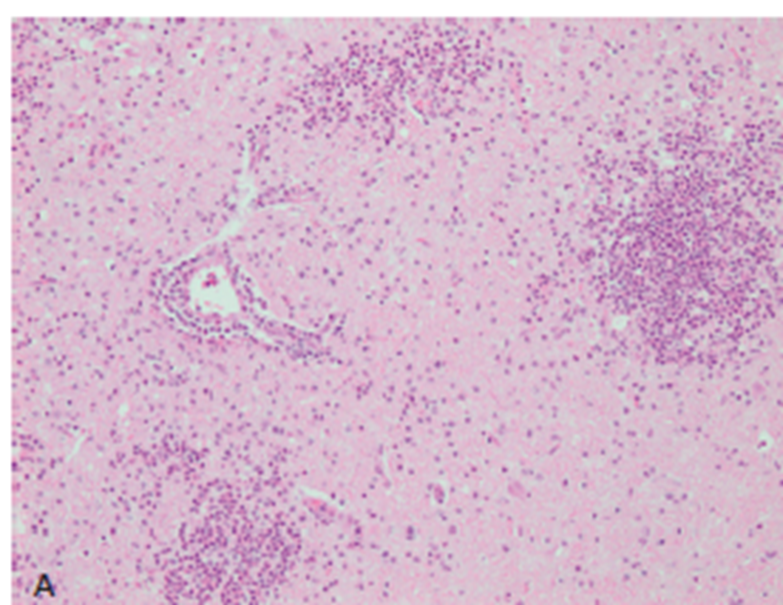

What pathology is shown in this image?

Trigeminal nerve schwannoma